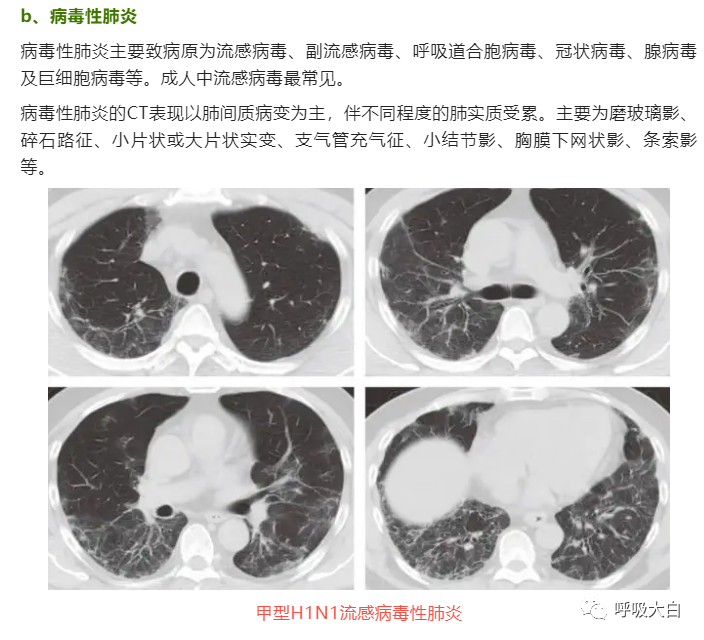

反晕征是一种特殊的胸部 CT征象,表现为环状高密度影围绕着中央密度较低的肺部阴影。起初认为,反晕征为隐源性机化性肺炎的特征性的征象;但此后被报道见于多种其他疾病,如肺副球孢子菌病、肺淋巴瘤样肉芽肿病、肺结节病、侵袭性肺真菌病、活动性肺结核及肉芽肿性多血管炎( 原韦格纳肉芽肿),亦可见于继发于感染或胶原血管病的机化性肺炎。

在隐源性机化性肺炎,反晕征中央的磨玻璃影的病理基础是肺泡间隔的炎症和细胞脱屑及少量终末气腔内的肉芽组织, 而外周的环状高密度影则对应远端气腔( 细支气管、肺泡管、肺泡腔) 内的纤维机化。表现为反晕征的结节病,外周的环状高密度影对应着多发的肉芽肿。肺隐球菌病则对应着肉芽肿性炎,PAS 染色可见着红色荚膜的隐球菌。肺结核的 CT环状高密度影对应的病理是上皮样肉芽肿,伴或不伴干酪样坏死,抗酸染色阳性或阴性。

在肉芽肿性疾病,其外围的环状高密度影不光滑, 而在非肉芽肿性疾病,外围的高密度影则较为光滑,此特征可用于初步判断病理性质。